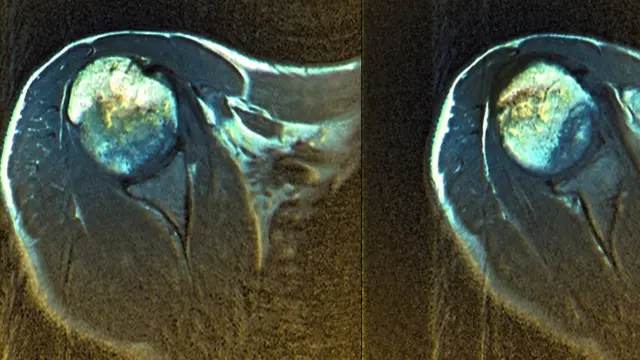

Fuente de la imagen, Science Photo Library